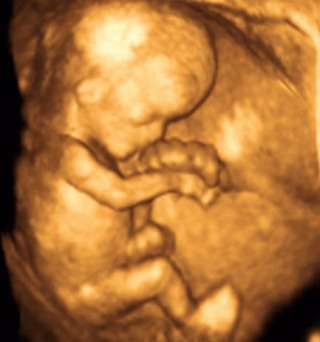

ECHOGRAPHIE FOETALE, GYNECOLOGIQUE eT DU SEIN .